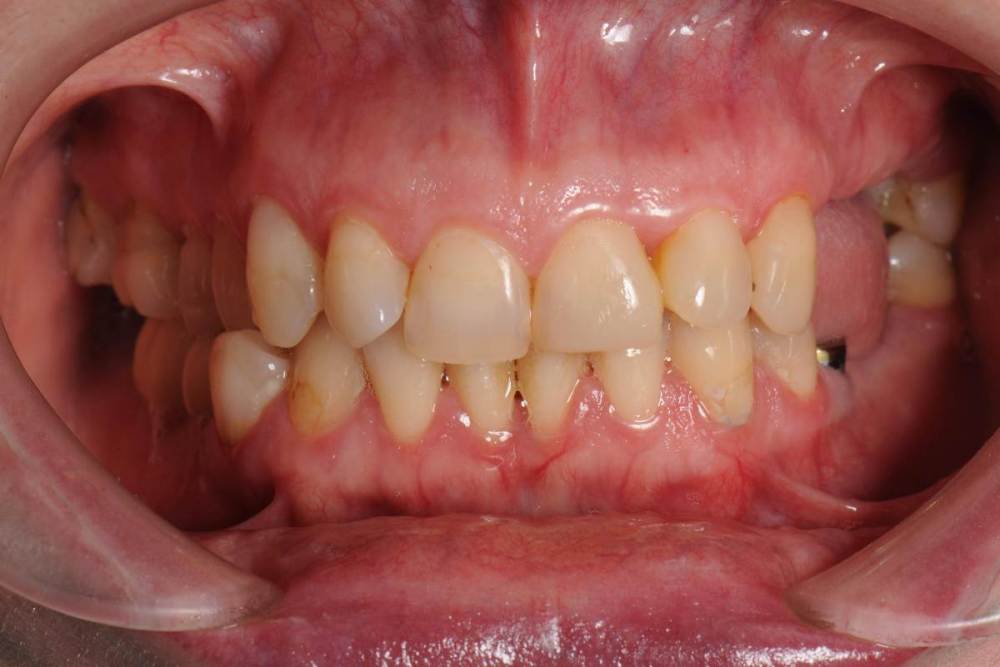

После ортодонтии и имплантации(делал не я):

21276649_.thumb.JPG.ac6bc70f88acb74ec8f69200429a4628.JPG

DSC_6448.thumb.JPG.8410ca5b1d184dbe575abfe993920475.JPG